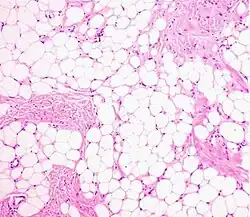

Histopathology of a lipoma: The mass is composed of lobules of mature white adipose tissue divided by fibrous septa containing thin-walled capillary-sized vessels.[25] H&E stain. -